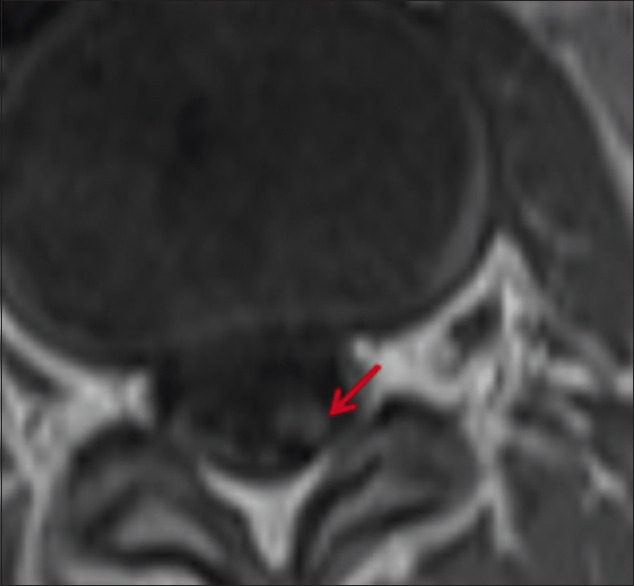

原发性弥漫性脑膜原始神经外胚层肿瘤是一种罕见的脑膜肿瘤,可伪装成慢性脑膜炎。虽然临床表现和放射学特征可为这种疾病提供线索,但脑膜活检是确诊的关键。在这种情况下,对经验性治疗无效的神经感染病例进行重新评估时,必须保持高度的怀疑和较低的门槛。我们介绍了一个 9 岁男孩的病例,他因慢性脑膜炎伴脑积水开始接受抗结核治疗。脑膜活检显示他患有原发性弥漫性脑膜原始神经外胚层肿瘤。

Primary diffuse leptomeningeal primitive neuroectodermal tumor is a rare meningeal neoplasm which can masquerade as chronic meningitis. While the clinical presentation and radiological features may provide a clue to this condition, meningeal biopsy is essential to clinch the diagnosis. A high index of suspicion and a low threshold for re-evaluating cases of neuroinfection that do not respond to empirical therapy are essential in this scenario. We present the case of a nine year old boy who was initiated on antituberculous treatment for chronic meningitis with hydrocephalus. Meningeal biopsy revealed a primary diffuse leptomeningeal primitive neuroectodermal tumor.